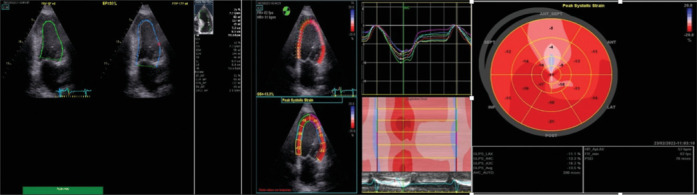

Methods: This prospective observational study included eighty recently diagnosed HFrEF patients with left ventricular ejection fraction (LVEF) ≤35%, prescribed the four pillars of guideline-directed medical therapy, and uptitrated to the maximally tolerated doses. The study included two groups: the ARNI group included forty patients prescribed ARNI, and the ACEI group included forty patients prescribed ACEI. All patients underwent two- and three-dimensional (2D and 3D) echocardiography to assess baseline parameters, including indexed left ventricular (LV) volumes and 2D and 3D GLS, at baseline and after a 6-month follow-up period.

Results: Both groups had no significant differences regarding demographic data and echocardiographic findings at baseline. After a 6-month follow-up period, there was a significant reduction in LV-indexed volumes in the ARNI group (P < 0.001) and indexed left atrial volumes (P = 0.013) compared to the ACEI group. There was a significant improvement in the ARNI group regarding LVEF (P = 0.011), 2D GLS (P < 0.001), and 3D GLS compared to the ACEI group, but no significant change in the LV mass index. Multivariate regression analysis showed that the use of ARNI, absence of diabetes mellitus, and a higher baseline GLS (above-9.1%) are independent predictors for the occurrence of reverse remodeling (defined as an increase in LVEF ≥5%).

Conclusion: The inclusion of ARNI in the pharmacotherapy of HFrEF patients is an independent predictor of LV reverse remodeling, as observed in a significant improvement in both 2D and 3D volumetric echocardiographic parameters, improved LVEF and longitudinal LV systolic function, represented in 2D and 3D GLS. Baseline 3D GLS and not LVEF or 2D GLS can help predict the occurrence of reverse remodeling in HFrEF patients.